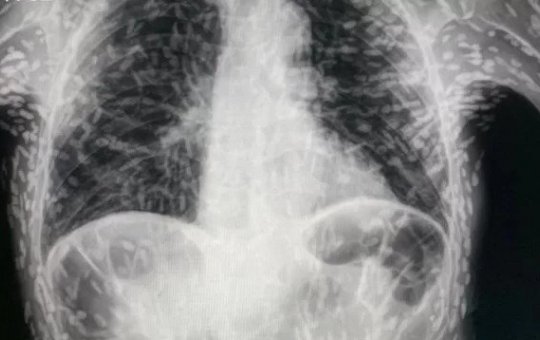

Raio-x chocante mostra tórax de paciente repleto de ovos de tênia

Caso foi revelado através de uma conta no twitter